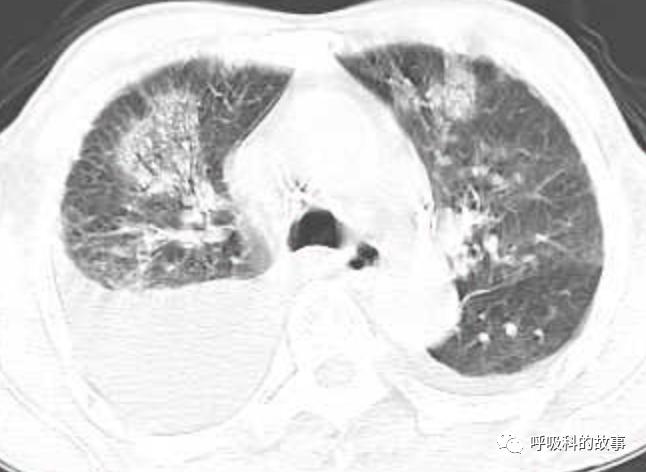

接着,我打开电脑看病历:患者,男,68岁,主诉:发热、头痛伴乏力10余天,咳嗽4天。肺部CT一看是右下叶大片实变肺炎,双侧少量胸腔积液,两上肺内中带片絮状斑片状影。2020.11.30 在外院检查 PCT 7.42ng/ml,ALT 199U/L,AST 250U/L,白蛋白24.7g/L,CRP 108.7mg/L,乳酸脱氢酶LDH388U/L(正常50-240),钾3.27mmol/L;血常规:白细胞4.9*10^9/L,中性85.2%。在外院给予了亚胺培南2天和本院美罗培南治疗2天后,效果并不理想。

(6)肺部影像以大叶性肺炎为主,其他部分是合并肺水肿的影像;